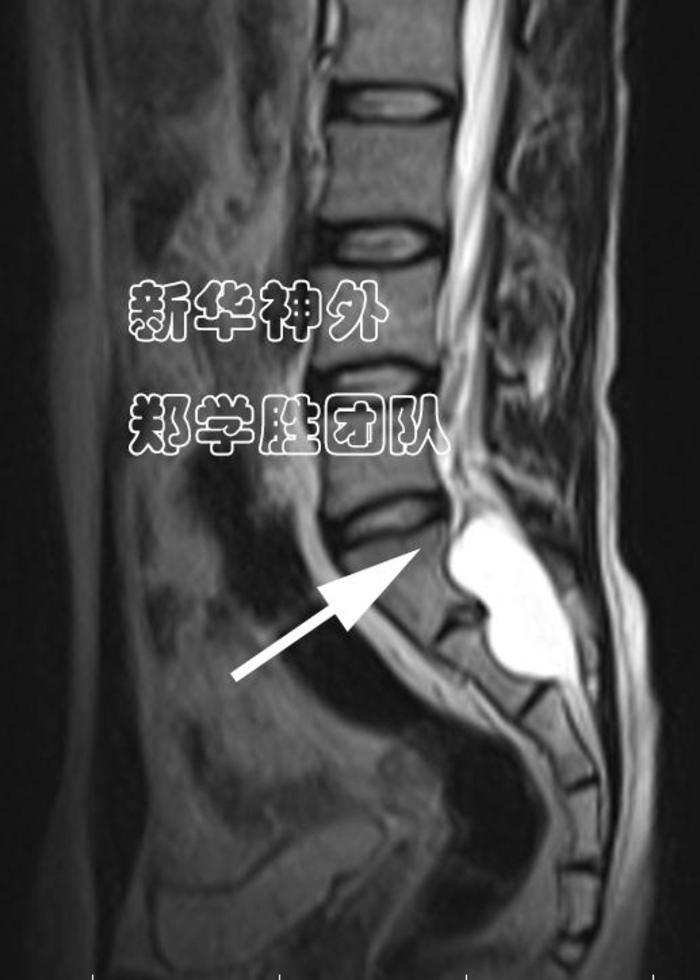

术后复查MRI:漏口(箭头所指)完全封堵。

术后症状逐步改善。